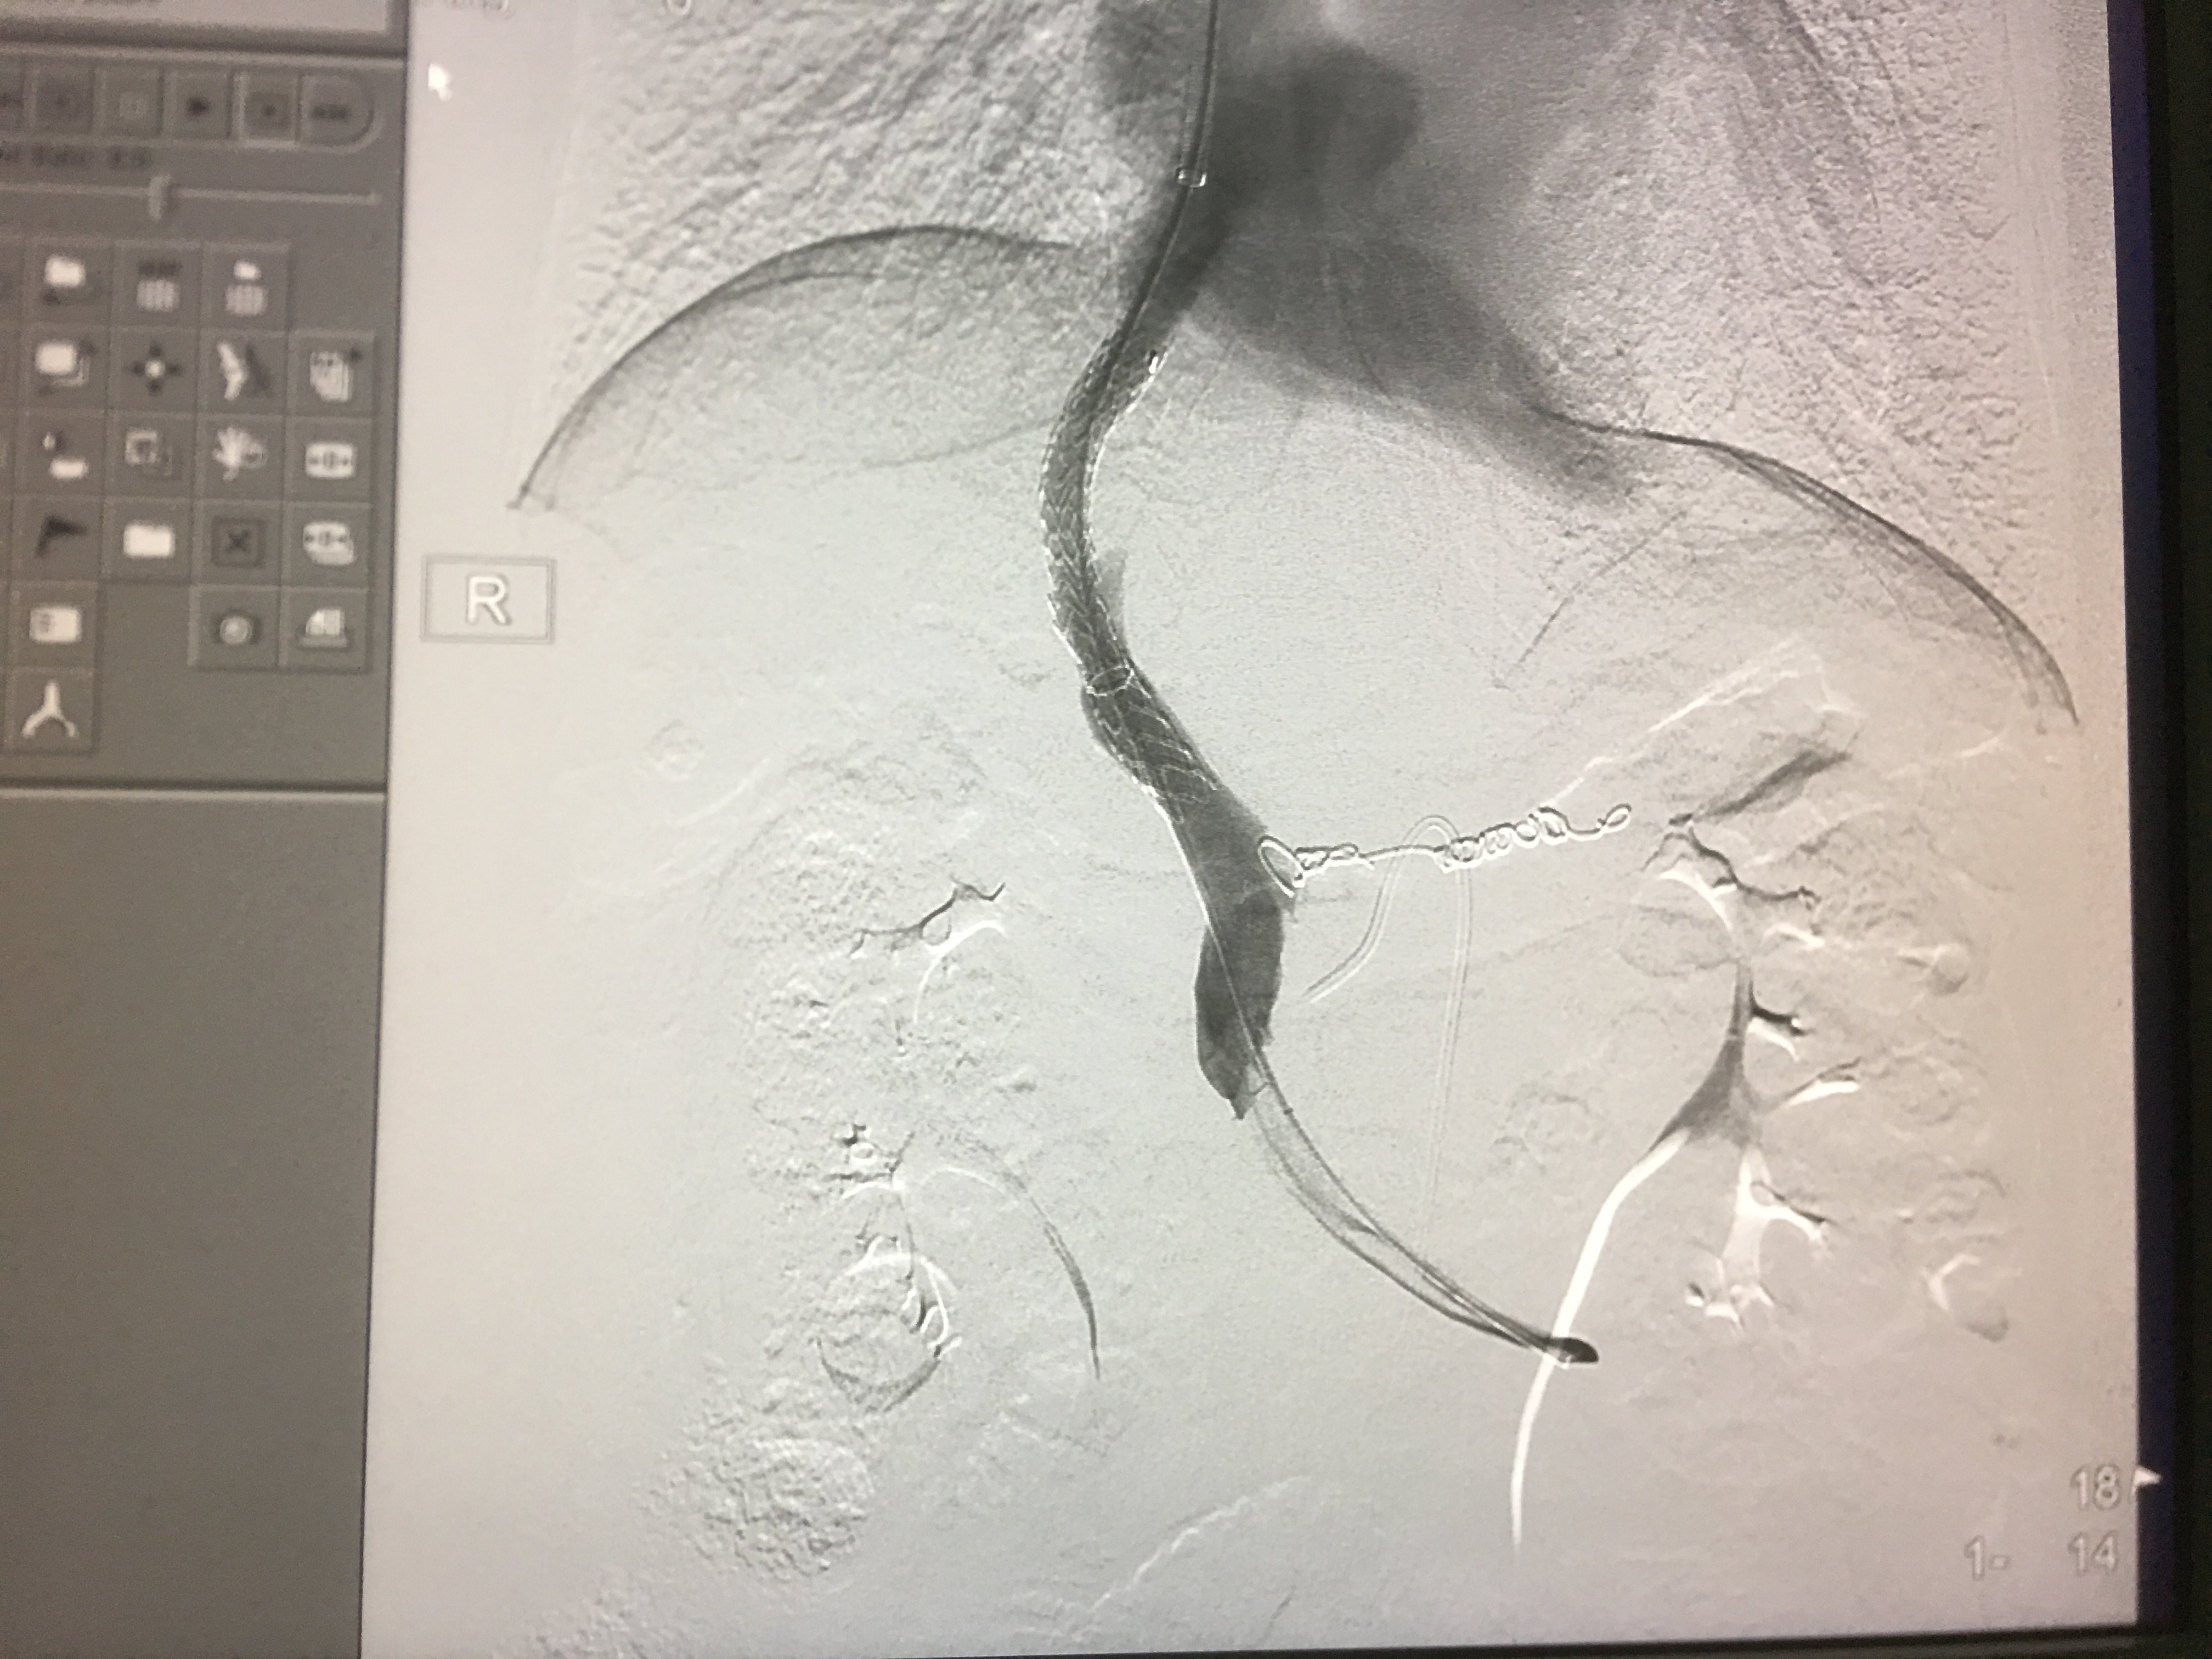

胃底静脉曲张栓塞

球囊扩张